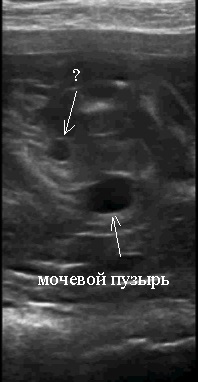

мочевой пузырь определяется, также визуализируется анэхогенное включение ближе к мочевому пузырю, предположительно мочеточник ?, на той стороне где отсутствует почка.

? мочеточник слева, анэхогенное полостное образование, расположенное ближе к мочевому пузырю.